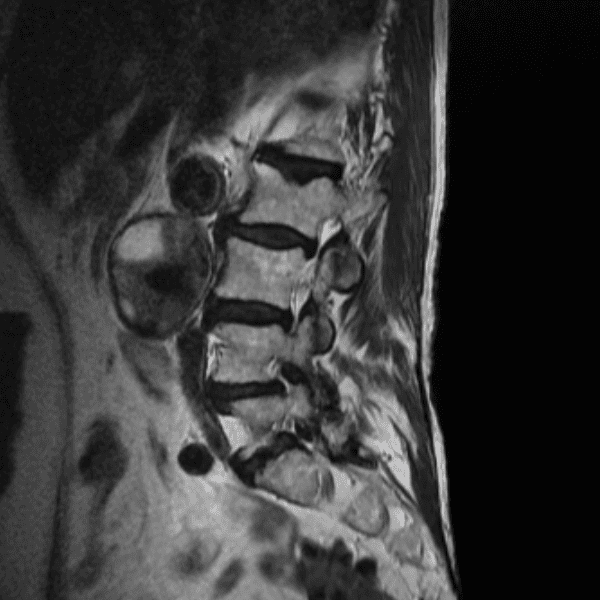

Simulates call by including subtle or difficult cases and some normals.

35 cases